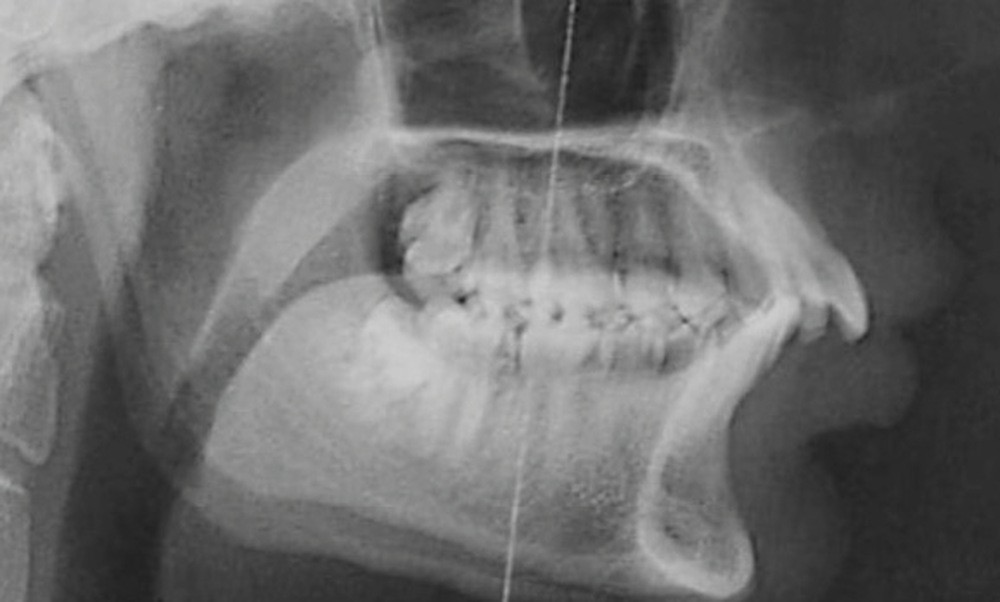

C’est à ces questions que nous permettront de répondre les deux premiers conférenciers, parodontologistes : le Dr Béatrice Straub nous présentera le renfort parodontal minéralisé, technique qu’elle a développée et pratique depuis de nombreuses années, pour éviter les préjudices des mouvements orthodontiques à risque, notamment lors des décompensations préchirurgicales (fig. 1a-d) ; le Pr Anton Sculean abordera le thème des greffes, avec leurs indications, les différentes techniques à privilégier et illustrera ses propos par de nombreux cas cliniques aux résultats esthétiques impressionnants.

Cette imagerie moderne montrera encore toute sa pertinence, au cours de la présentation du Dr Arnaud Lafon qui nous fera partager son expérience des transplantations dentaires. Longtemps considérée comme le « marronnier » de l’orthodontie, cette technique bénéficie maintenant d’un protocole bien établi et se révèle être une alternative très intéressante à l’implantologie, notamment chez les adolescents ou en cas de budget réduit. Solution immédiate, elle est parfaite lors d’avulsions des premières molaires mandibulaires cariées dans un protocole ortho-chirurgical. Plus besoin d’attendre la mise en place des troisièmes molaires pour envisager le geste de propulsion mandibulaire !